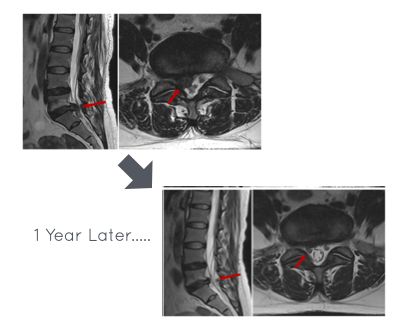

The bigger the disc herniation, the better it shrinks...📉 Spontaneous Disc Regression in different herniations occurs as folllows: -Sequestration - 96% -Extrusion - 70% -Protrusion -41 % -Disc Bulging -13% Complete herniation Resolution is seen in - 43% of Sequestrations -

The bigger the disc herniation, the better it shrinks...📉

Spontaneous Disc Regression in different herniations occurs as folllows:

-Sequestration - 96%

-Extrusion - 70%

-Protrusion -41 %

-Disc Bulging -13%

Complete herniation Resolution is seen in

- 43% of Sequestrations